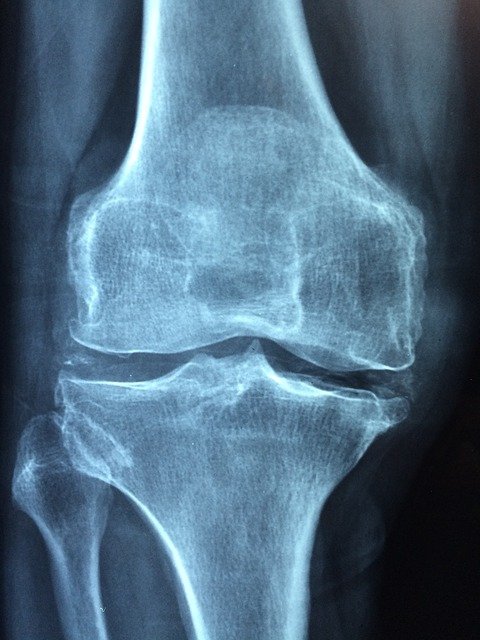

1. 관절염 및 골관절염 완화

MSM은 관절 염증 감소와 유연성 향상에 도움이 된다고 합니다. 한 연구에 따르면 관절염, 무릎 및 허리 통증, 관절 통증 등의 증상을 앓고 있는 사람들이 MSM을 복용하면 이러한 증상들이 완화된다고 합니다. MSM은 신체가 새로운 관절과 근육 조직을 형성하는데 도움이 되는 동시에 관절 부종과 경직을 유발하는 염증 반응을 낮추는데도 도움을 줄 수 있다고 합니다. MSM은 우리 몸의 면역 체계에 도움을 주고 세포 활동을 촉진하는 방식으로 이어지기 때문에 인공적인 치료보다 자연스럽고 효과적인 항염증제라고 합니다.

골관절염 환자 약 120명의 관절 통증에 MSM의 효과를 분석하기 위해 실험을 했는데 MSM 보충제를 약 12동안 꾸준히 섭취한 결과 부기 및 통증, 관절 운동성이 개선된 것으로 나타났습니다. MSM 보충제는 글루코사민과 함께 사용을 한다면 대부분의 사람들에게 부작용 없이 염증과 통증 완화에 도움을 주는 것으로 확인이 됐습니다. MSM 보충제는 관절염에 도움을 주는 훌륭한 자연 치료제라고 합니다.